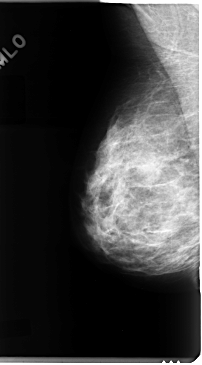

C_0091_1.LEFT_MLO

LEFT_MLO LINES 4712 PIXELS_PER_LINE 2544 BITS_PER_PIXEL 12 RESOLUTION 50 NON_OVERLAY